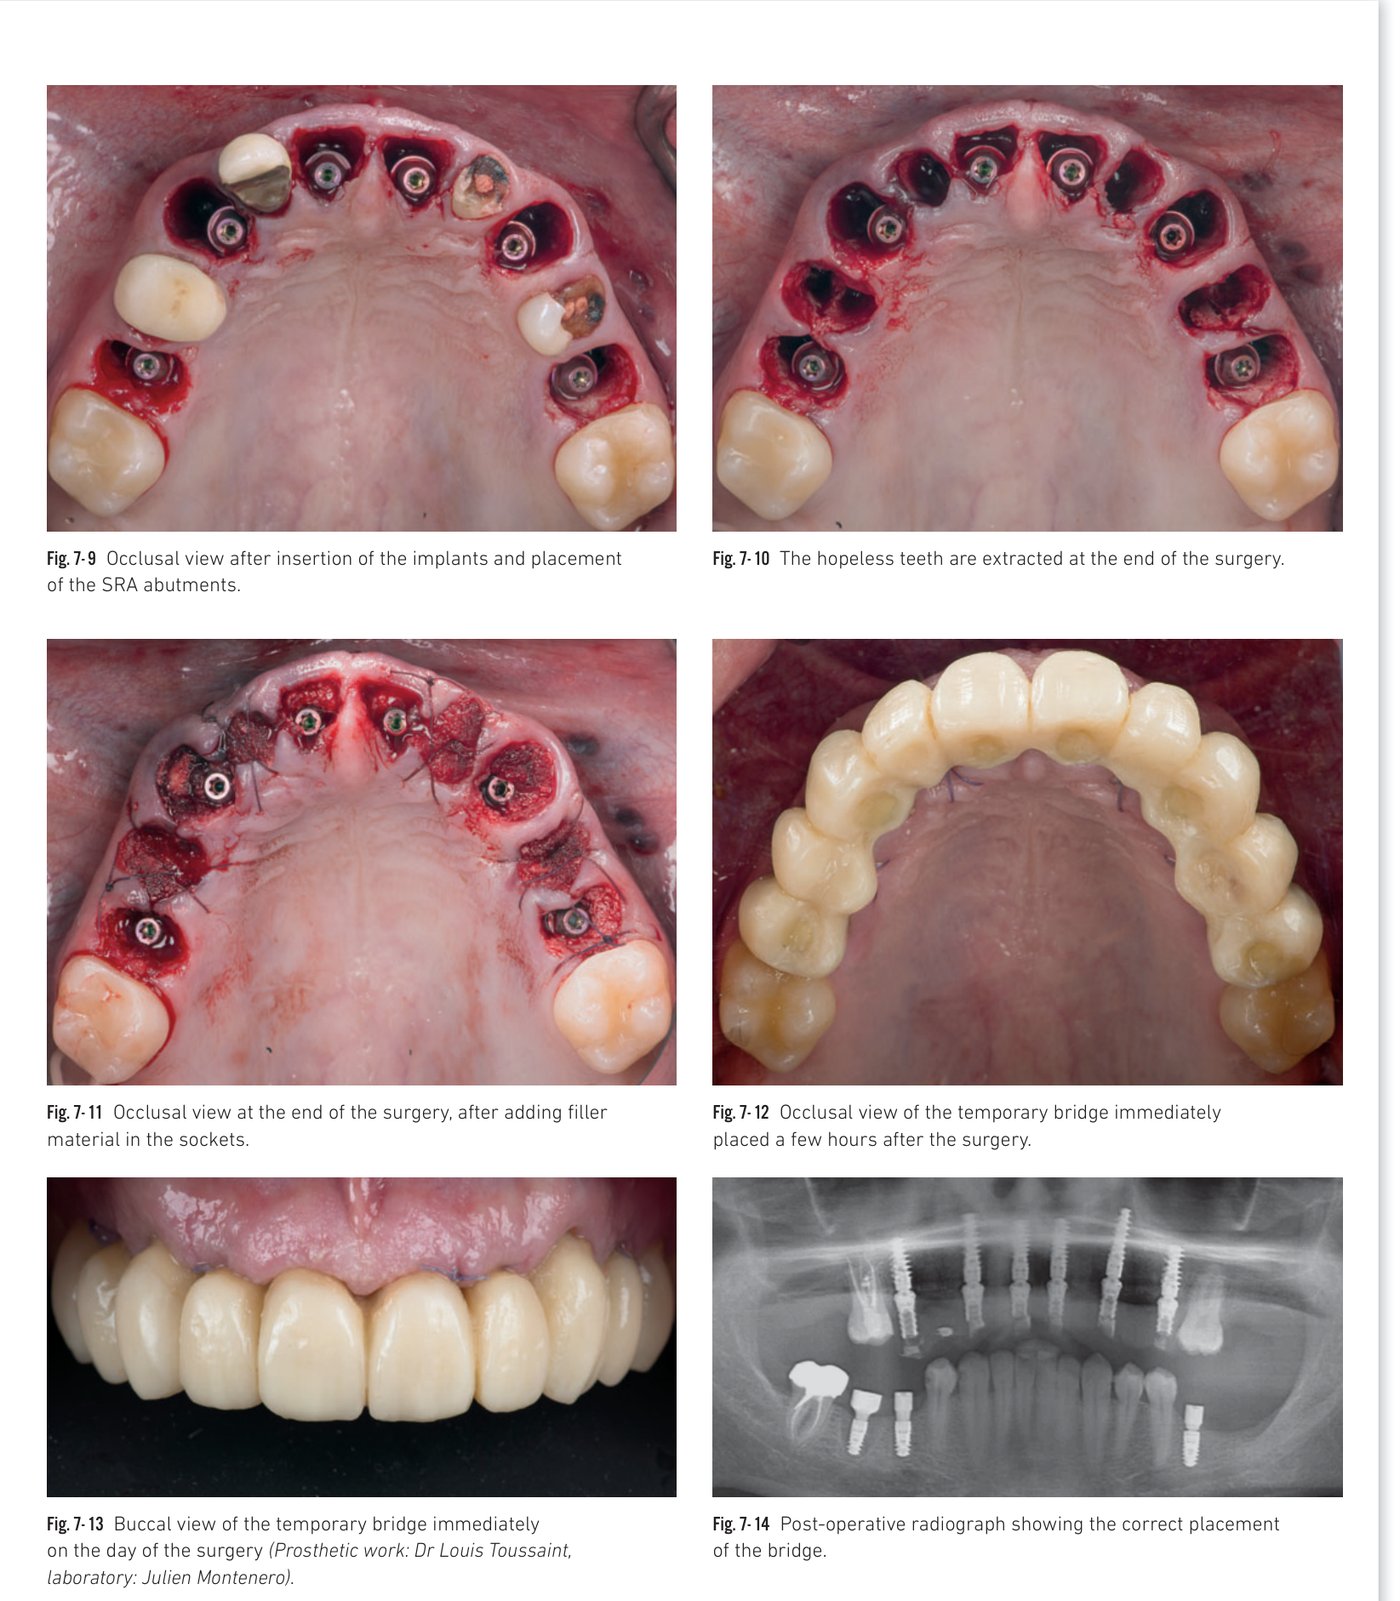

Treatment of a maxillary full arch with immediate loaded implants

Healing of Bone Level implants under a complete removable denture can lead to bone resorption, cover screw exposure, or implant failure. Immediate loading, in addition to patient comfort, makes the treatment more reliable. Success depends on sufficient primary stability and an accurate protocol for impression-taking and fabrication of the immediate temporary bridge.

In this case, two distal implants were angulated along the anterior sinus wall to avoid a sinus lift procedure. SRA abutments were used to correct axial discrepancies while maintaining a sealed connection at bone level. A customized impression tray (duplicate of the complete denture) was hollowed out at implant sites to register implant positions with plaster.

Clinical situation 7, page 2: Guided surgery and BLX insertions

Clinical situation 7, page 3: Immediate temporary bridge and post-operative X-ray